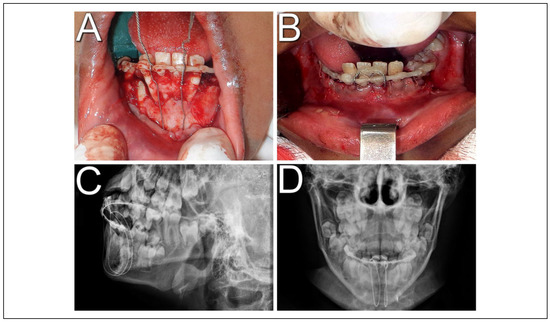

In second intervention, the use of titanium mini screws was not feasible due to the thin alveolar bone wall, as the stabilization of the screws could not be achieved, in addition to the risk of damage to dental germs. So, another treatment modality was chosen. Up with a new dental splinting, proceeded with a circummandibular cerclage using steel wire number 1, encompassing the base of mandible and the alveolar segment, bilaterally, between teeth 31 and 32 and between 41 and 42 (Figure 2A and B). In the immediate postoperative radiographic examination, a satisfactory fracture reduction and cerclage positioning were observed (Figure 2C and D). With this technique, greater stability of the dentoalveolar fragment and occlusion was achieved, allowing the local healing process. The patient received postoperative recommendations, mainly to maintain a soft diet.

Figure 2. Surgical procedure. (A) Transoperative photograph showing dentoalveolar segment stabilization by a circummandibular wire associated with a new dental splint; (B) intraoral photography in immediate postoperative period; (C) postoperative skull radiography in lateral position; (D) postoperative skull radiograph in posteroanterior position.